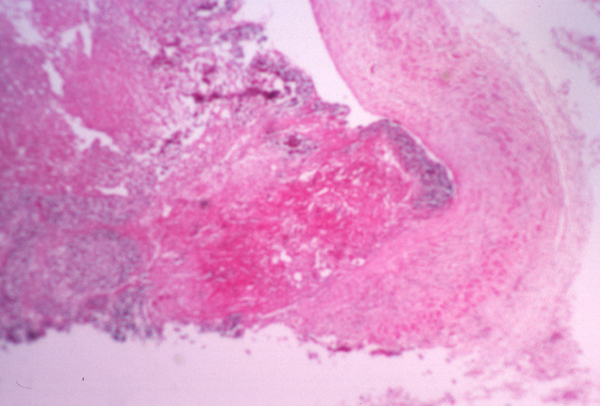

018